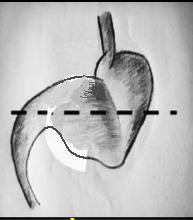

Volvulus de type

mesenterico axiale |

Type mixte de volvulus

de estomac |

Hernie hiatale par roulement

avecvolvulus gastrique de type mesenterico-axiale du

segment hernie du corps gastrique . Image

radiologique TDM en coupe sagitale . |